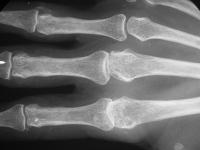

Rheumatoid metacarpophalangeal joint changes, metacarpal head.

Click for larger image

Pre and postop radiographs.